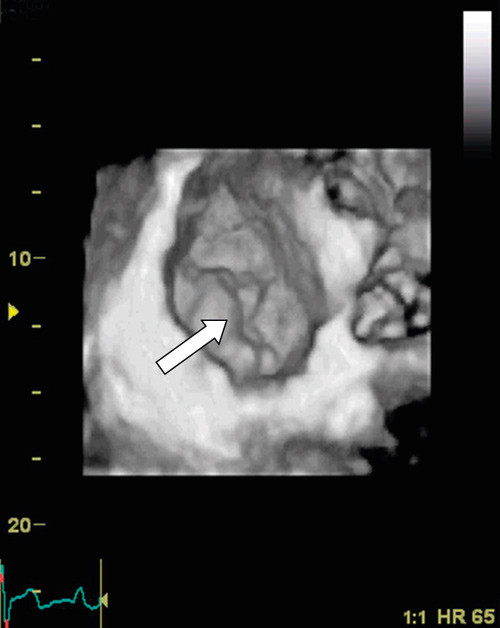

The evaluation of heart valve disease using 3D echocardiography has been validated in different studies. To date, the best documented have been diagnostic studies of pathological mitral valves (9) – (12). During the last decade, there has been a change in the surgical treatment of mitral valve disease. New surgical techniques have enabled the repair of mitral defects in many patients who would previously have had to have valve replacement. Reparative surgery of this kind requires a very high degree of precision in diagnostics of the mitral valve’s form and function, to enable the correct surgical method to be employed. In our own department, we use 3D echocardiography to investigate patients with mitral valve regurgitation, to enable us to locate exactly the damage to the valve (Figure 2). We have benefited especially from the so-called «surgeon’s view» from the left atrium, where the entire mitral valve can be represented in the same image as shown in Figure 2.

Figure 2  Transthoracic recording of the mitral valve viewed from the left atrium («surgeon’s view»). The white arrowhead…

Figure 2 Transthoracic recording of the mitral valve viewed from the left atrium («surgeon’s view»). The white arrowhead marks prolapse of the posterior mitral valve seal, which comprises the medial and posteromedial thirds (P2 and P3, respectively).